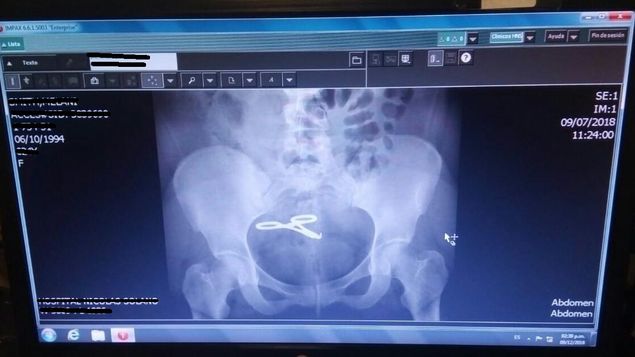

La mujer de 35 años contó que vivió cuatro años con una pinza dentro de su vientre tras una cesárea que le practicaron en el Hospital Santo Tomás.

La bocatoreña Melanie Smith, de 35 años, casi muere luego de que especialistas de la maternidad del Hospital Santo Tomás, le dejaron en su vientre una pinza cuando le realizaron la cesárea mediante la cual dio a luz a su criatura.

La denuncia que Melanie Smith realizó la sustentó en los documentos de su historia clínica en los que se puede apreciar que en hallazgos postoperatorios dan fe de la causa por la cual ella perdía sangre.

Sacar la pinza de su vientre es el menor de los problemas que enfrenta actualmente, pues como la pinza permaneció cuatro años dentro de su abdomen, esta se le adhirió al intestino delgado, razón por la cual tuvieron que extirparle gran parte de este órgano.